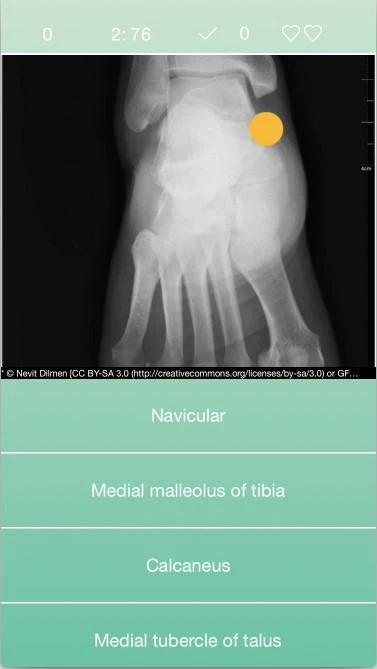

RadiologyPocketGame: Um novo aplicativo para estudar anatomia radiológica (Android)

RadiologyPocketGame é mais uma ferramenta para quem quer estudar anatomia radiológica. Este aplicativo usa imagens de várias modalidades de diagnóstico (radiologia convencional, tomografia computadorizada e ressonância magnética) para testar seus conhecimentos.